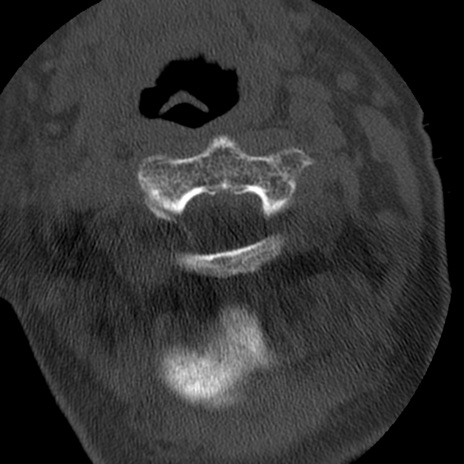

症例50 頚椎CT(横断像)

【症例】60歳代女性

【主訴】後頭部〜右後頸部にかけての痛み

【現病歴】本日飲食店でコーヒーを飲んでいたところ、突然後頭部〜右後頸部にかけて痛みが出現し、右上肢の感覚障害を伴ったため救急要請。

【身体所見】脳神経学的に明らかな異常所見を認めず。右上肢に軽度の感覚障害あり。

異常所見と診断は?

頚椎CT